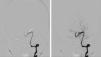

Patients and methodsA case is presented of trigeminal neuralgia caused by vertebral artery compression. An analysis of the microsurgical technique, as well as a systematic review of the literature about this uncommon nerve compression is performed, in order to investigate, by pooled case analysis, if MD is a good option for this type of patient.

ResultsA total of 7 studies were included for analysis, to which the present case was added, making a total of 56 patents. There were excellent results in 53 cases, and partial recovery in 3, with a mean follow up of 54 months. No major complications were found.

DiscussionThe good clinical results and absence of postoperative mortality or severe morbidity in our pooled case series lead us to recommend MD as the preferred treatment for TN caused by VD in patients in whom major surgery is not contraindicated.